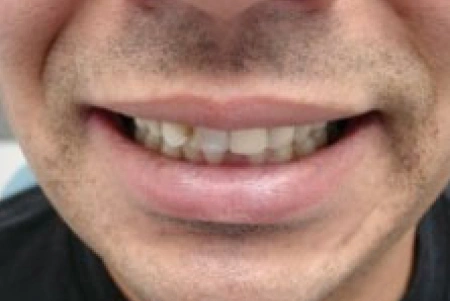

Before

After